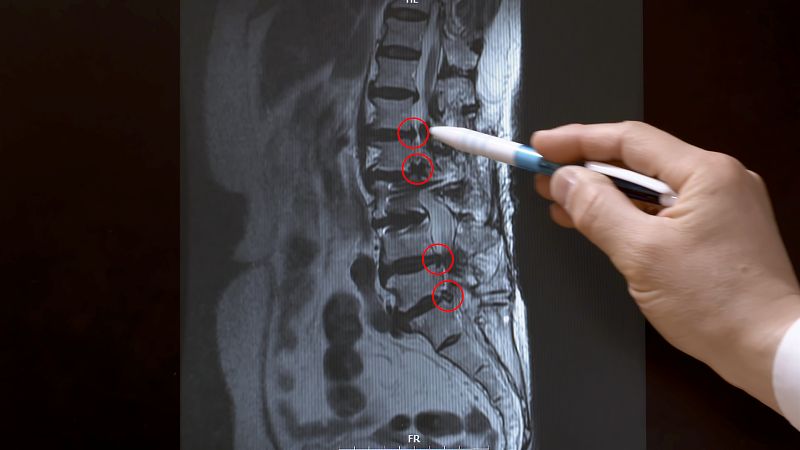

척추뼈는 우리 몸을 세우고 균형을 잡는 역할과 함께 뇌에서 나오는 신경다발이 지나가는 신경 통로의 역할을 한다. 신경 다발이 지나가는 통로를 척추관이라고 하는데 이 척추관이 좁아져 신경을 눌러 다양한 증상을 유발하는 질환을 척추관협착증이라고 한다.

그런데 왜 여성은 다리 통증을 호소한 것일까? 실제로 많은 척추관 협착증 환자가 허리가 아닌 다리 통증을 호소한다. 이는 척추관을 지나가는 신경이 다리로 이어지기 때문이다. 좁아진 척추관으로 인해 다리로 내려가는 신경의 일부가 눌리면서 다리의 통증과 저림 등 다양한 증상이 나타나는 것이다.

척추관 협착증은 증상에 따라 총 다섯 단계로 진행되며 치료의 시기를 놓치지 않는 것이 중요하다. 걷는 것을 두려움으로 만드는 척추관 협착증. 과연 원인은 무엇일까? 정형외과 명의 김용찬 교수와 함께 척추관 협착증이 발생하는 원인과 단계별 증상, 치료의 골든타임 등을 명쾌하게 알아본다.